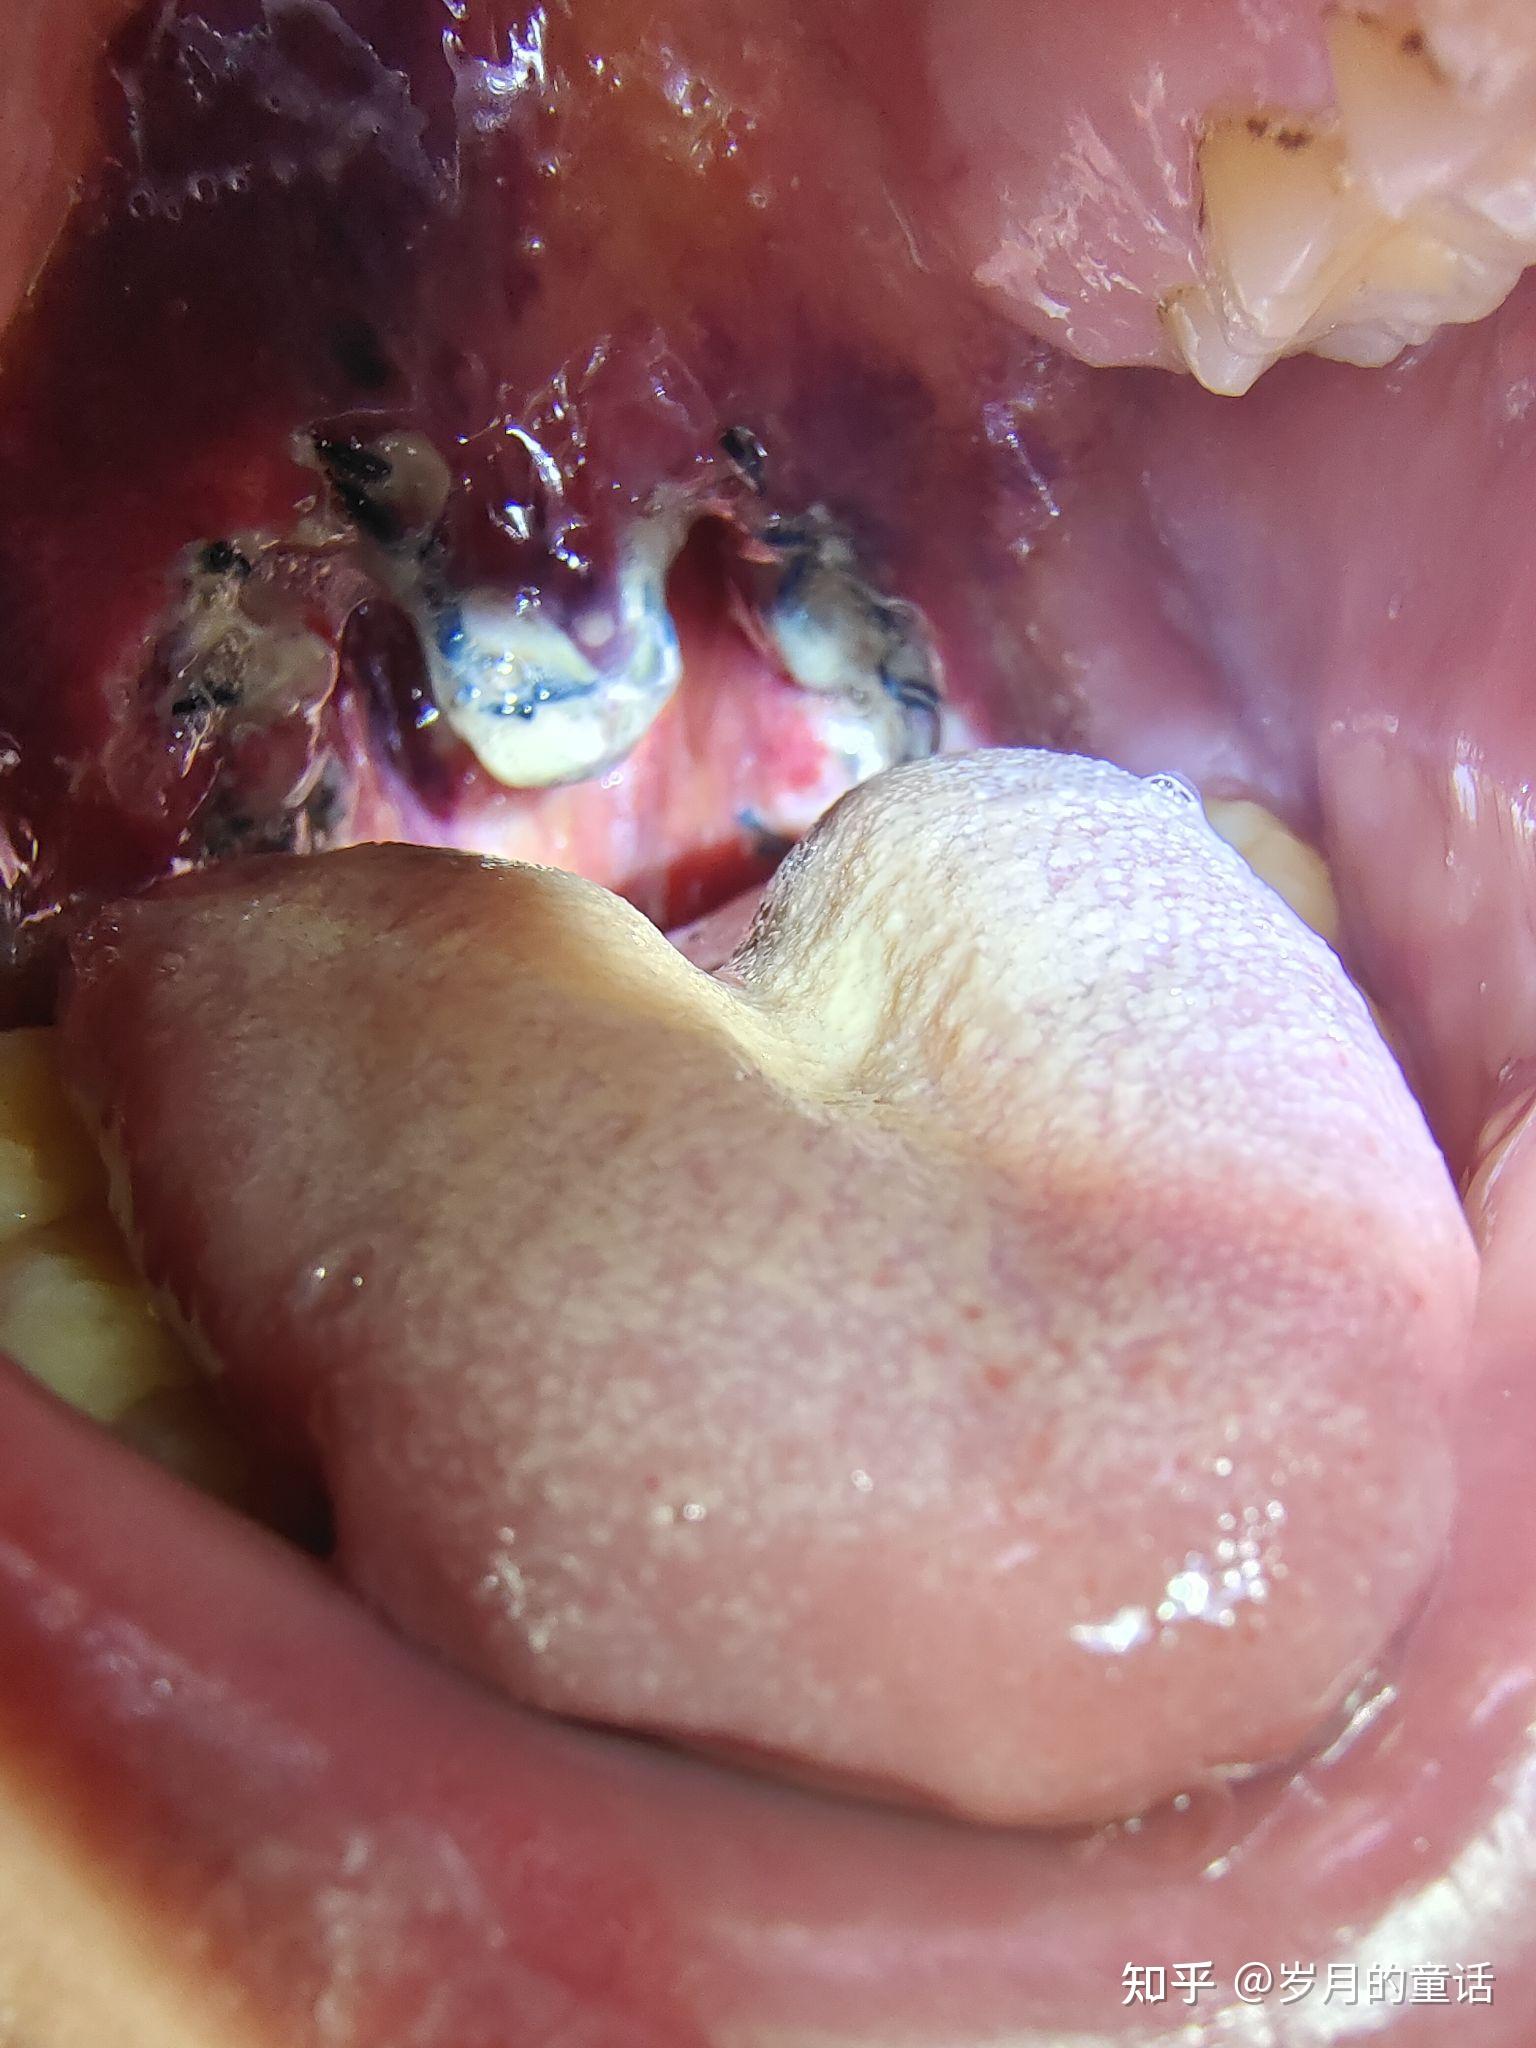

扁桃体切除手术的体验是怎样的? - 知乎

图片尺寸3024x4032